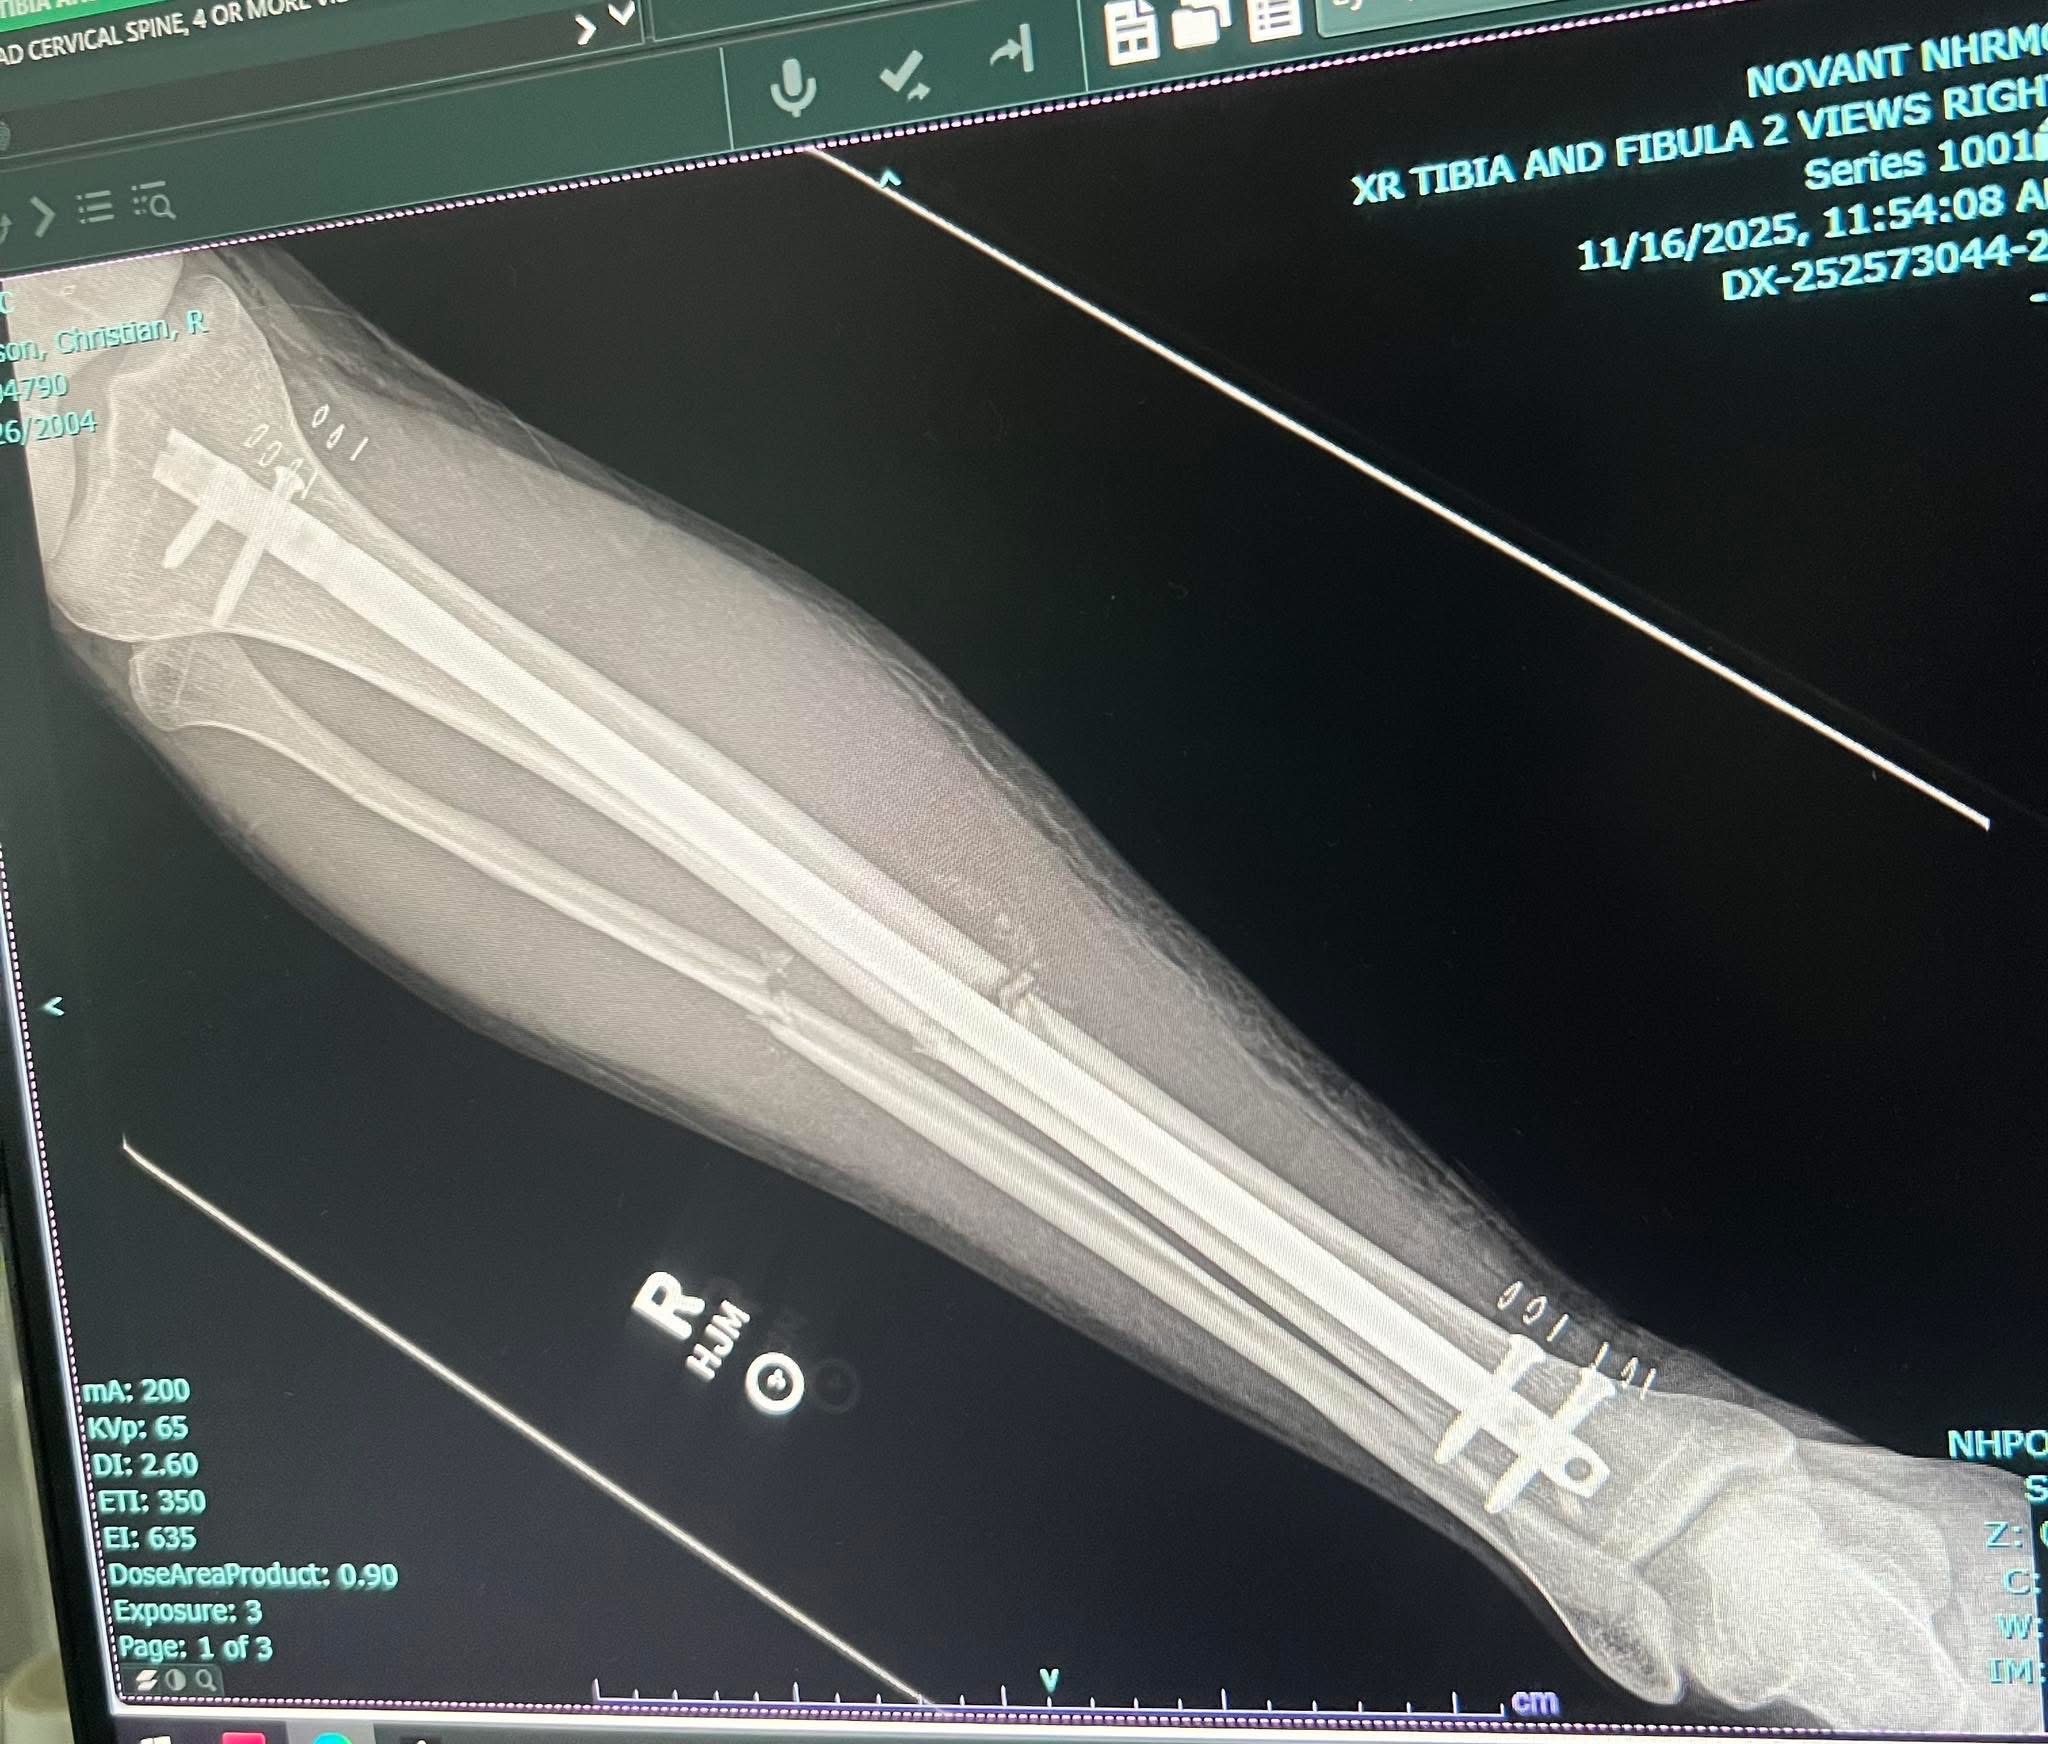

So as many of you know already Christian (my son) fell in a ditch and broke his leg in 3 places he broke his tibia in half and fibula in two places. His tibia required surgery and they inserted about a foot long rod held in by four screws. His fibula is still broke as that is not a weight-bearing bone so they figured they would let it heal on its own. He is currently walking on a walker when he is able to, at the moment that’s not a lot. He does start physical therapy next week thankfully they will come to his home to do this as he is obviously not able to drive . However, unfortunately, he had just signed on his new home two days prior. He also has other bills and many co-pays and medical bills to come as he probably has about a three months healing / recovery process. He was the only one working as his fiancé Asia stayed home full-time with their 6 month old daughter Saylor. And now she also has to help take care of him and the baby he’s not one to ask for a handout but given the circumstances, I figured we would post this as many family and friends have asked how they could help right now we thought this would be the best way to help ease his burden so he is able to focus on healing over the next couple of months. If you’re not able to help, we completely understand as we are near the holidays. Prayers are always appreciated. Thank you so much in advance.